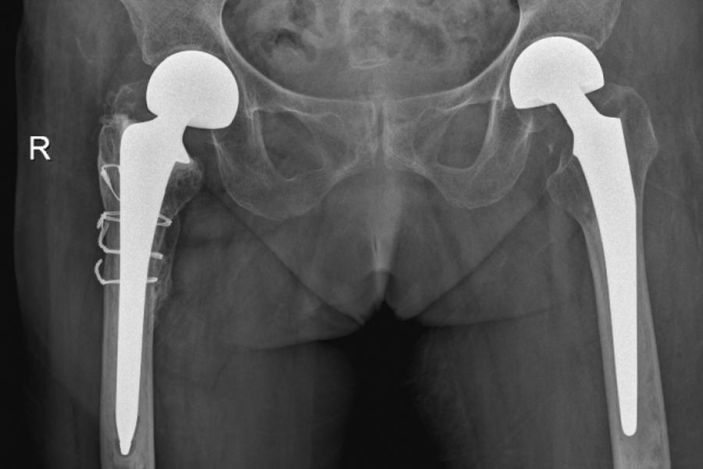

△右側(R)是賴婆婆3年前跌斷股骨術後,左側是本次手術術後。

經過悉心診治,賴婆婆恢複良好,術後2天已經能通過助行器下床站立和适量行走,将于近期康複出院。據了解我院骨科在10月15日、16日兩天時間,包括上述的賴婆婆在内,連續收治了3名高齡患者,其中2名近百歲、1名90歲。她們都因不慎跌倒導緻股骨骨折,現都已成功接受了股骨手術,身體恢複良好。